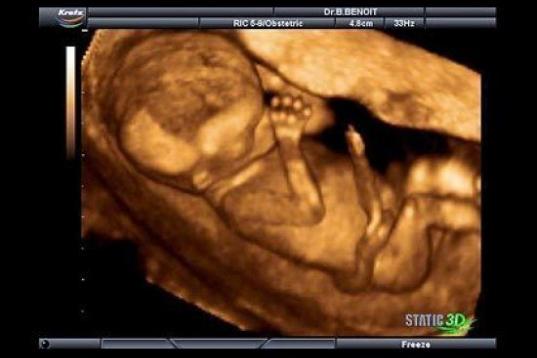

En esta galería puedes ver en fotos como es el desarrollo de un feto de semana en semana:

Desarrollo del feto, en fotos